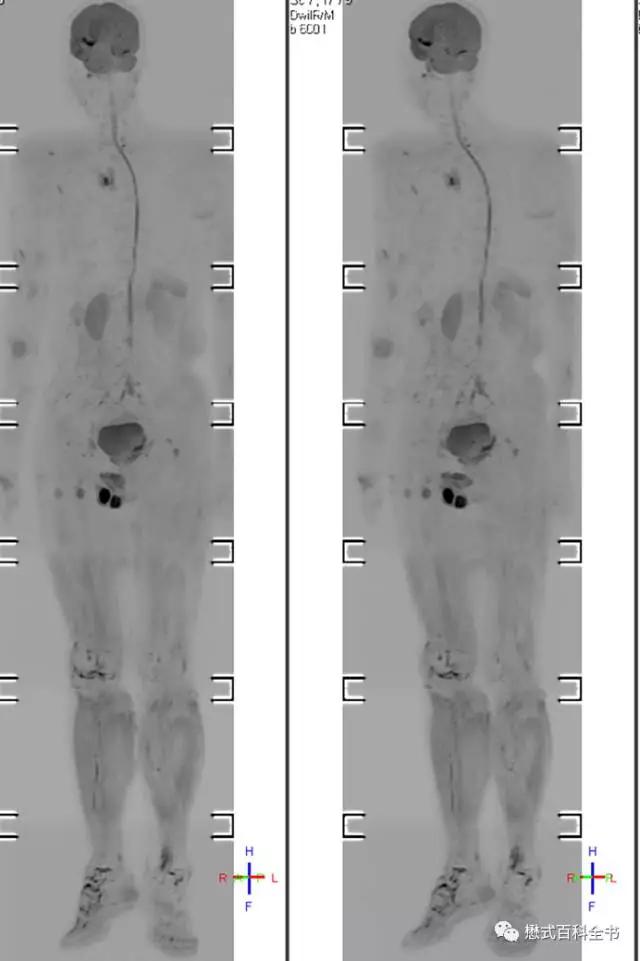

除了这个,还有一个特殊的应用,全身弥散成像。某公司又把这种技术叫做类PET。当然,本人觉得这样叫,有点不严谨。因为,毕竟磁共振全身弥散DWIBS和PET的原理千差万别,这样叫多了,怕引起自己人和临床医生歧义。

全身背景抑制的弥散DWIBS,可以用来做全身弥散扫描,筛查肿瘤及有无全身转移灶。

图17:DWIBS全身背景抑制弥散